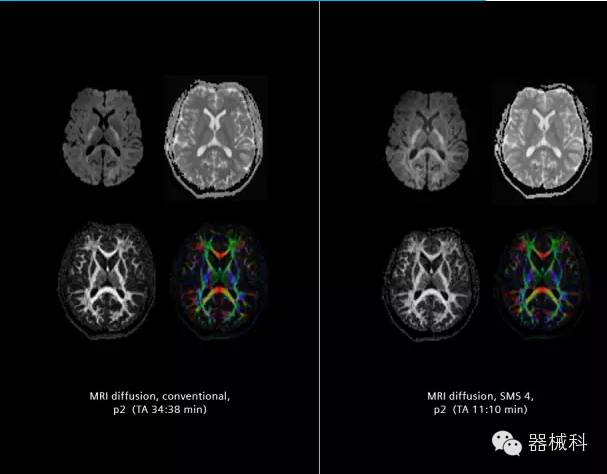

在2015年RSNA上,西門子隆重發(fā)布了Simultaneous Multi-slices 技術(shù)(即同時多層采集技術(shù),簡稱SMS),這是磁共振掃描技術(shù)中第一次引入“同時多層”的概念,此概念技術(shù)的發(fā)布,將對未來磁共振成像領(lǐng)域帶來巨大的變革!

SMS將高級成像技術(shù),尤其是神經(jīng)系統(tǒng)彌散成像時間縮短68%。

SMS技術(shù)可以將原本用于科研的高級成像技術(shù)轉(zhuǎn)化成臨床常規(guī)

擁有了SMS“同時多層”采集技術(shù)之后,用戶可以在非常短的時間內(nèi)完成MR掃描,結(jié)合西門子靜音技術(shù),大大提高患者的舒適性,或在單位時間內(nèi)采集更多的數(shù)據(jù),也可以得到高精度、高準(zhǔn)確性、大數(shù)量的功能成像數(shù)據(jù),為臨床和科研提供強大的支持。專家認為,SMS“同時多層”采集技術(shù)未來在 提高成像質(zhì)量、外科手術(shù)計劃、降低術(shù)后神經(jīng)功能缺陷、提高fMRI的時間采集效率、提高靜息態(tài)功能磁共振數(shù)據(jù)質(zhì)量等方面將帶來深遠影響,希望該技術(shù)可以盡早面世,引領(lǐng)磁共振進入多層時代!